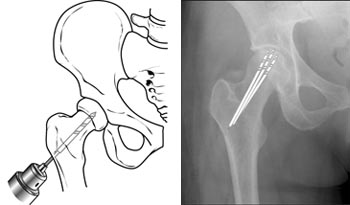

- Οστική αποσυμπίεση

Πρόκειται για τη δημιουργία οπών στη μηριαία κεφαλή με σκοπό την ελάττωση της ενδοστικής πίεσης και τη δημιουργία χώρου για την ανάπτυξη νέων αιμοφόρων αγγείων.

Εάν έχει γίνει έγκαιρη διάγνωση, με την αποσυμπίεση σε συνδυασμό με οστικά μοσχεύματα είναι δυνατό να αποφευχθεί η κατάρρευση της μηριαίας κεφαλής και η απώλεια της σφαιρικότητάς της καθώς και η συνεπακόλουθη αρθρίτιδα.

Η επέμβαση είναι επιτυχής στο 25% με 85% των περιπτώσεων.